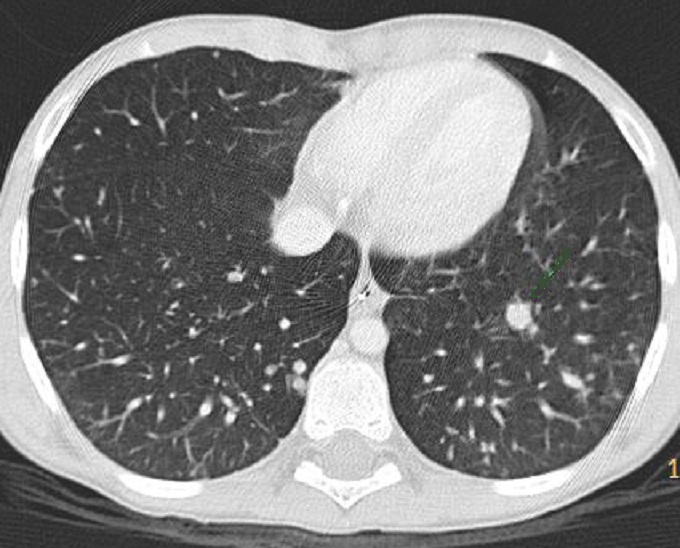

Nodules metastatique pulmonaire gauche et

a partie posterieure du poumon droit du tumeur

pancreatoblastome maligne . Image radiologique TDM

pulmonaire en coupe axiale , fenetre parenchymateuse

. |